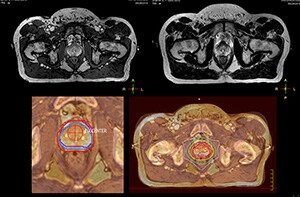

Beaumont Health System (Royal Oak, Michigan, USA) is one of the largest health systems in the USA, with eight hospitals and 153 outpatient sites, a medical school and a research institute. The Radiation Oncology (RO) department houses a dedicated Ingenia MR-RT solution that is routinely used for clinical and research MR-RT activities. “The main reason to integrate MR imaging in RT planning is the superb soft tissue contrast that allows detailed delineation of tumors and healthy organs, which is crucial for RT planning,” says Craig W. Stevens MD, PhD. “MR also provides information on functional and biological activities in tumors, background tissue and normal organs, which may also be used in RT planning,” says physicist Di Yan, DSc, FAAPM.” “We currently use MR-RT mainly in the abdomen and pelvis region: prostate, colorectal, pancreatic, cervical, and liver. Also in the brain, we are starting to use it,” says Dr. Yan.

“The biggest problem for CT-based planning, especially in prostate, is you can’t see the cancer very well,” says Dr. Stevens. “On CT it can be quite challenging to see the edge of the prostate especially at the apex. When the edge of the prostate can’t be delineated well on CT, radiation oncologists will increase their margins a little bit so they don’t miss it, but that can also increase toxicity.” “Using MR, the prostate is well delineated. We quickly see the edges of cancerous tumors like in prostate cancer, and as normal structures can be defined, we can optimize the treatment plan to protect these organs and their normal function. This can potentially improve the outcome. And it improves workflow as well. We can contour more quickly, confident that the tumor is going to be in the field.” “The Ingenia 3.0T MR scanner provides high resolution allowing us to make scans fast for the patients. It also gives the potential to include methods like MR spectroscopy and diffusion weighted Imaging, which we’re in the process of doing right now,” Dr. Stevens adds.

“When a patient registers, first CT simulation and MR simulation are done, followed by CT-MR registration on Pinnacle3. Then the target and normal organ delineation is performed on MR images. Meanwhile we create a reference CT image for online treatment and localization correction. During the treatment phase we can perform additional MRI scans to visualize the anatomy changes and create an adaptive plan. This plan basically adapts the treatment plan to the changes.” “Along with its great benefits, MR has introduced some new challenges,” Dr. Stevens says. “Radiation therapy teams generally have no experience with MR. The Philips training helped us to implement fully the things we can do with the Ingenia MR-RT system. So the training, as well as having a good MR physicist, is critical.”